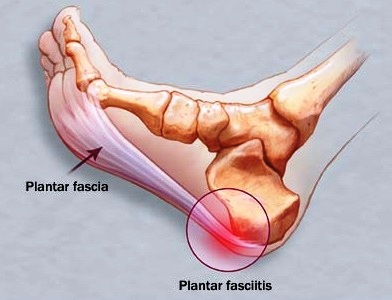

Dolore al Tallone

Si localizza al centro del cuscinetto del calcagno e si caratterizza per la presenza di dolore circoscritto o subito posteriore alla linea mediana. La causa precisa del dolore è sconosciuta ma le ipotesi più attendibili comprendono: intrappolamento dei nervi, fratture da stress del calcagno, infiammazione dell’inserzione calcaneare della fascia plantare e da stress meccanico, in età evolutiva in seguito al processo di accrescimento.

Patologie dei Tendini della Caviglia e del Retropiede

Comprendono: tendiniti, tenosinoviti, infiammazione delle inserzioni dei tendini o delle fasce, sublussazioni o rotture parziali o complete dei tendini. Il disturbo più frequente è il dolore progressivo che si accentua con il movimento. A volte una sollecitazione anormale del tendine interessato è causata da una deformità del piede o da una modificazione volontaria della meccanica della fase di appoggio, conseguenza del tentativo del paziente, di evitare il carico su una lesione dolente della fascia plantare, inaftti si ottengono benefici con l’uso di antinfiammatori.